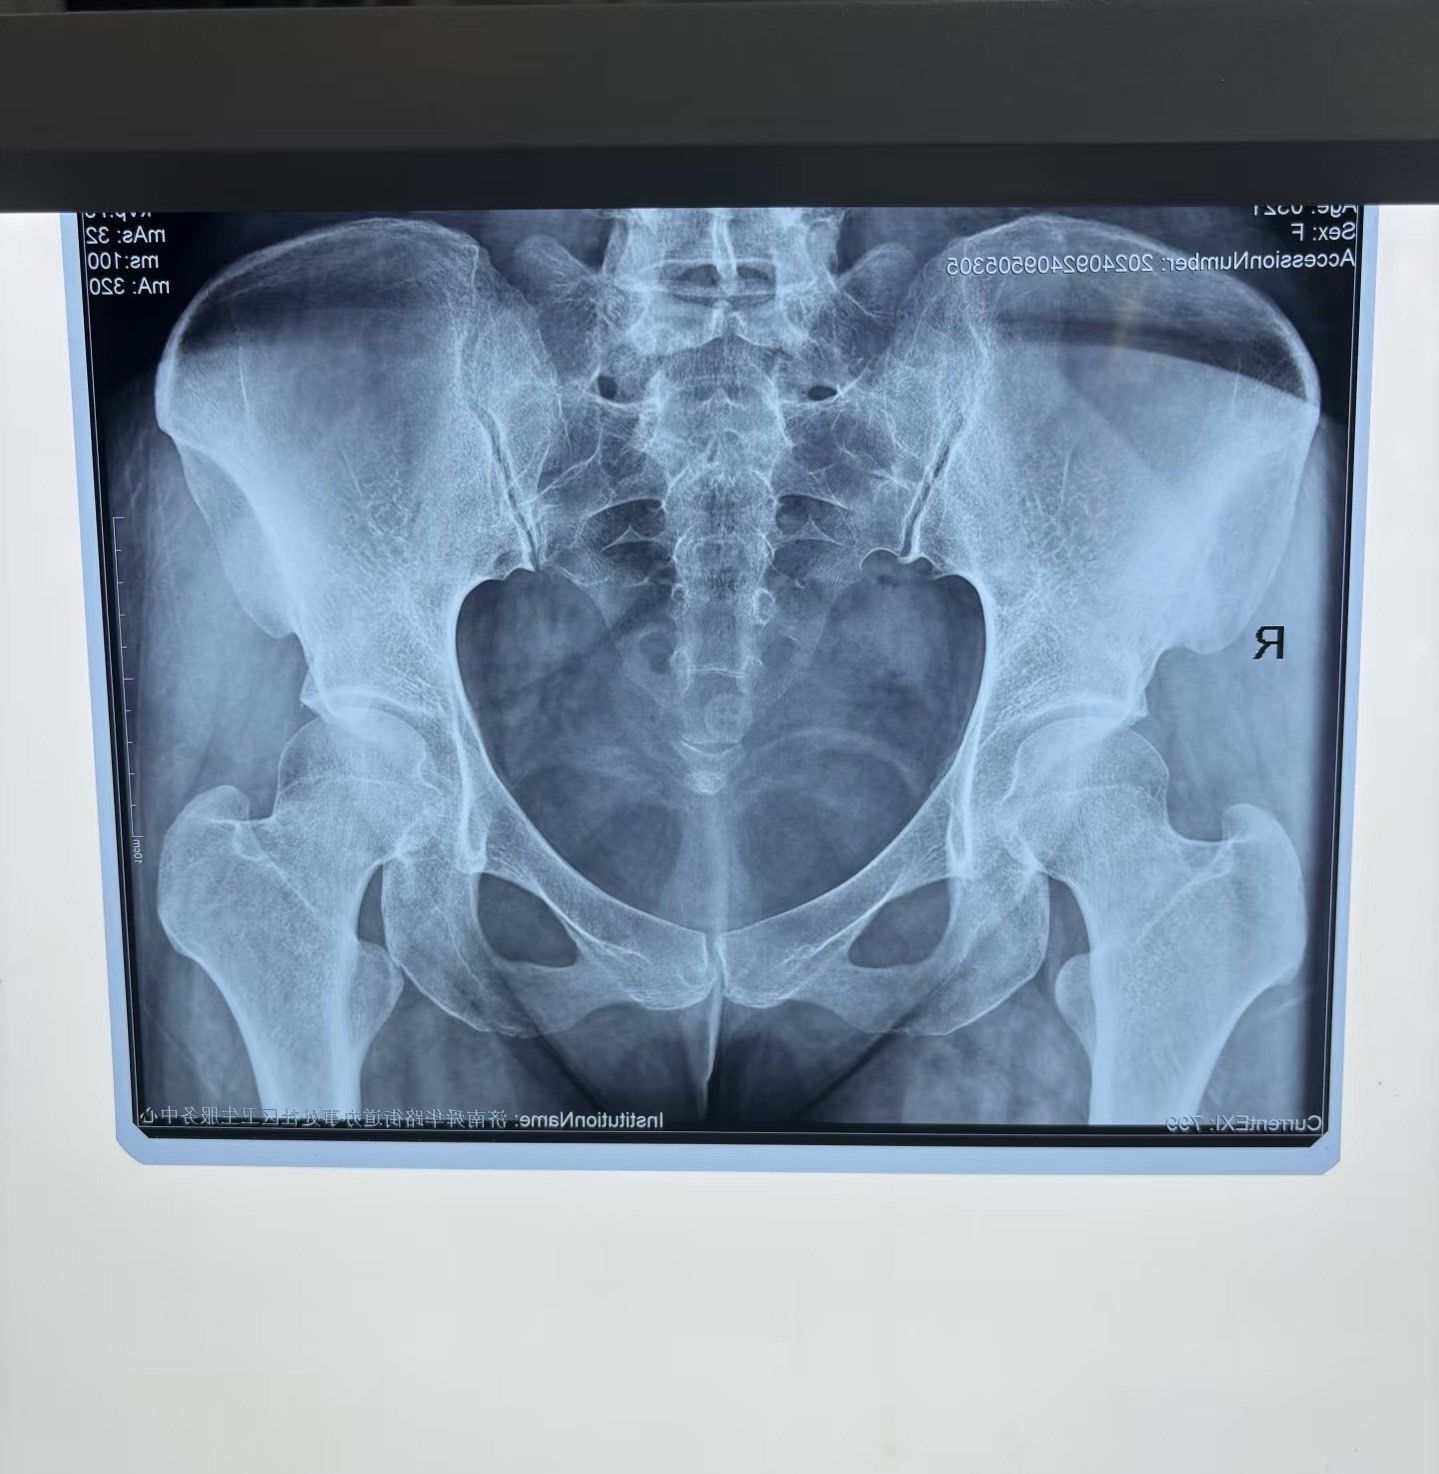

骨盆正位(髋臼发育不良,股骨头缺血性坏死,髋外翻)

骨盆修复,x光

骨盆x线解剖